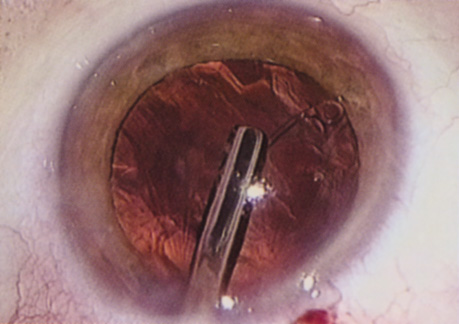

A mature cataract precludes visualization of the fundus. A B-scan ultrasonographic examination provides a real-time, two-dimensional (2D), cross-sectional image of the globe along the marked axis of the probe (Fig. 3). Cataracts are more common in patients with chronic retinal detachment, prior trauma, or intraocular tumors; therefore, a B-scan study is helpful in excluding structural posterior segment pathology before surgery on a mature cataract. Although a negative result to B-scan evaluation is reassuring, the surgeon should remember that it does not predict postoperative visual outcome. The B-scan can be thought of as a picture of Cincinnati from an airplane; the office buildings may all be standing, but you cannot tell whether the people in them are working.

Fig. 3. This B-scan ultrasound shows a normal looking posterior pole, without retinal detachment or intraocular mass. The vitreous cavity is echo lucent.